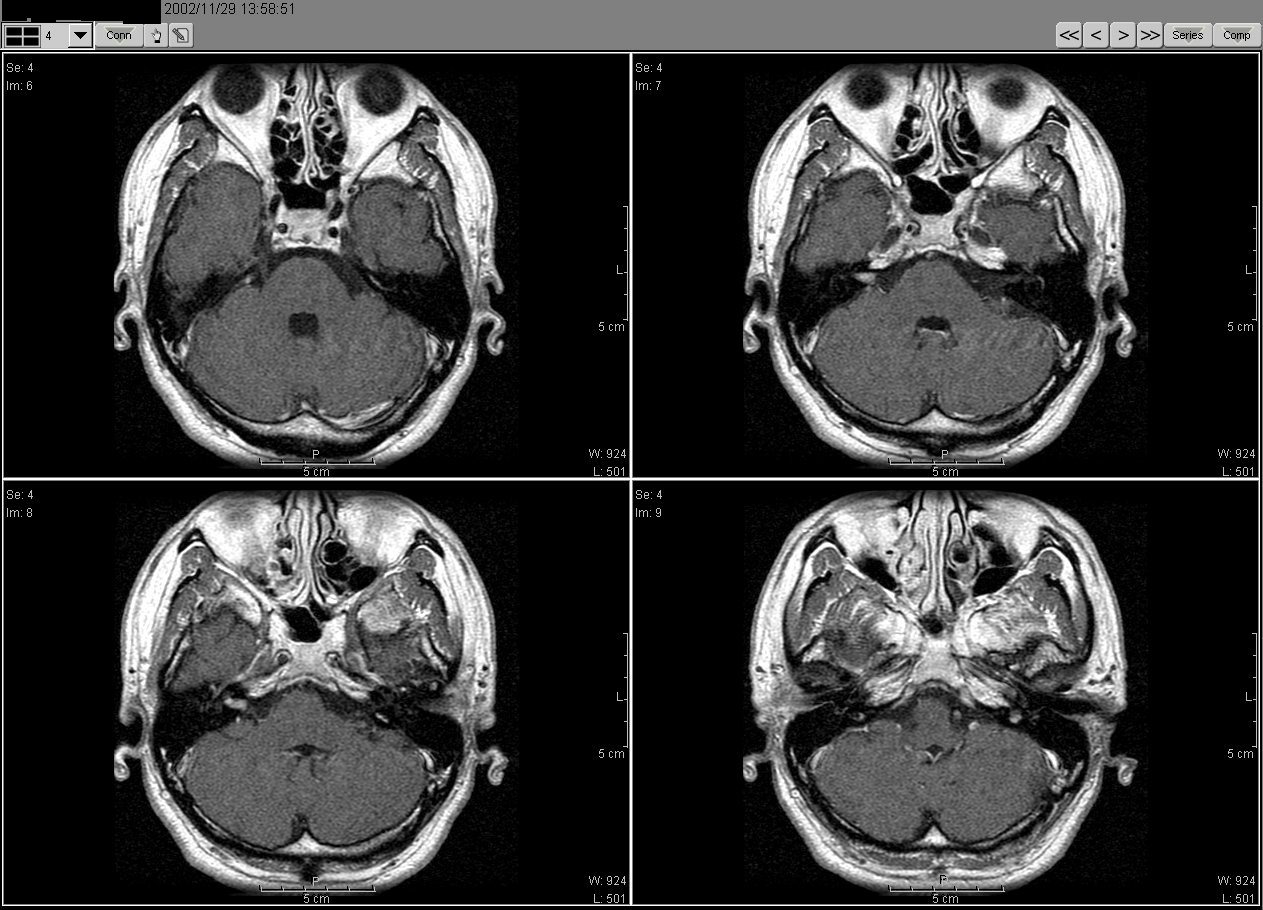

2002_11_11MRI01

2002_11_11MRI02